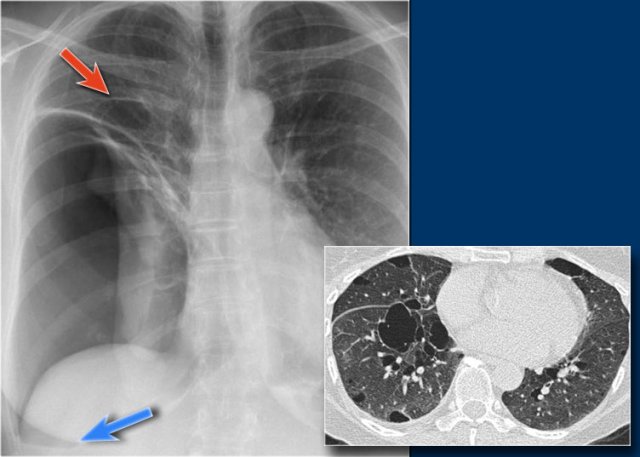

Diaphragm

The contours of the left and right diaphragm should be visible.

The right diaphragm should be visible all the way to the anterior chest wall (red arrow).

Actually we see the interface between the air in the lungs and the soft tissue structures in the abdomen.

The left diaphragm can only be seen to a point where it borders the heart (blue arrow).

At that point the interface is lost, since the heart has the same density as the structures below the diaphragm.